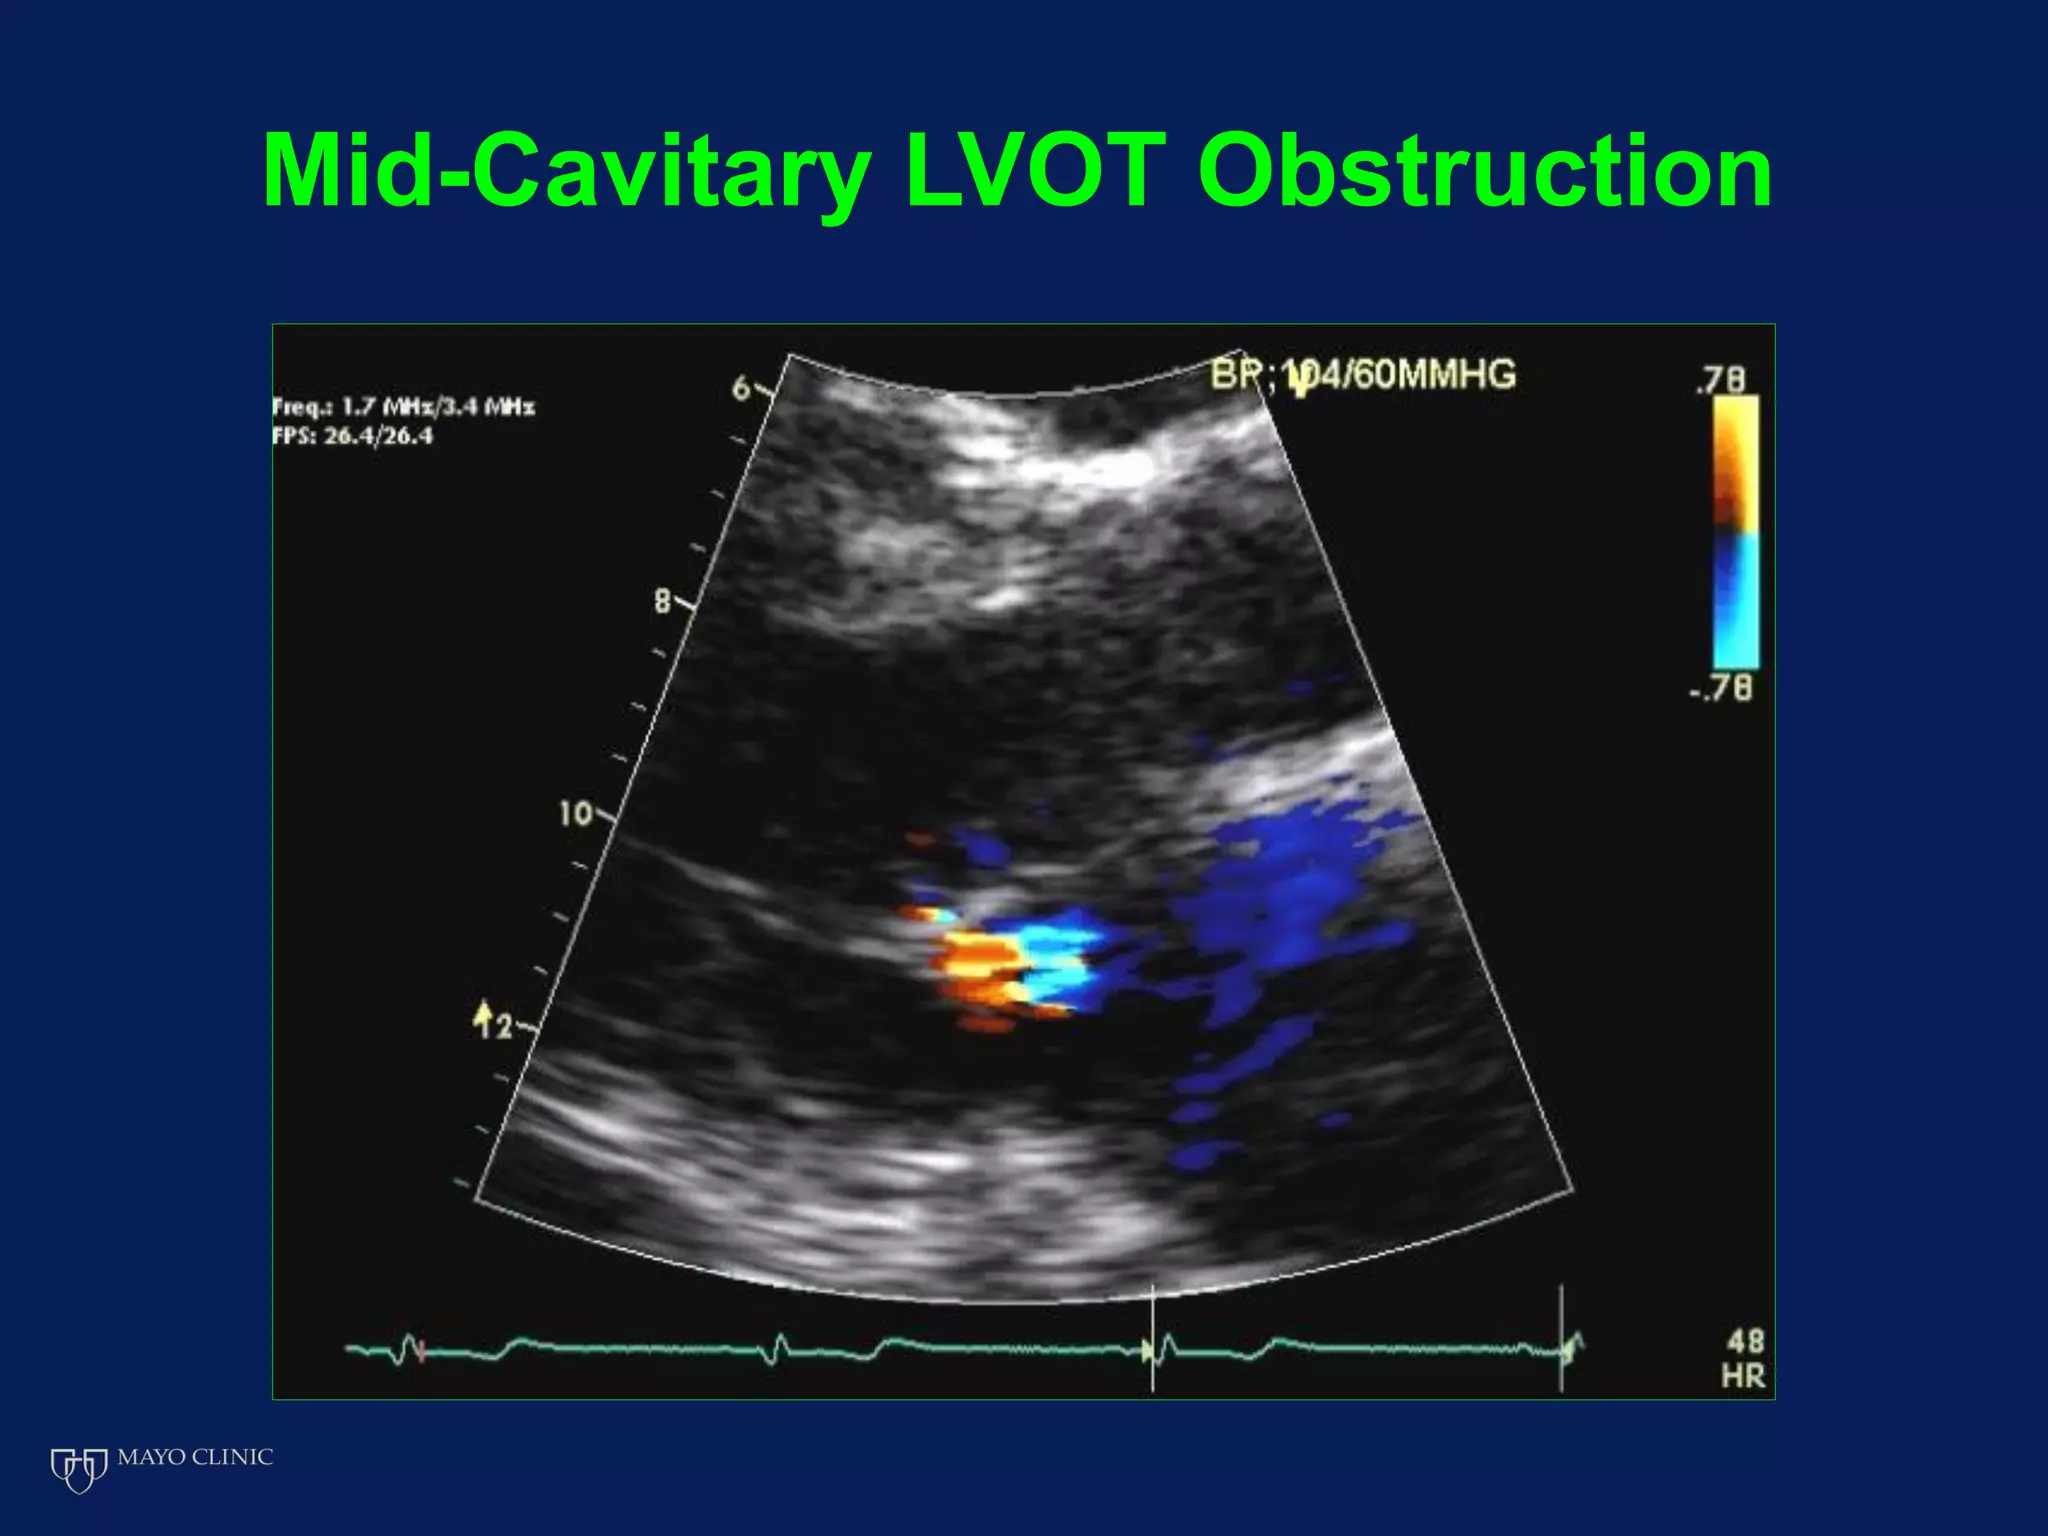

Echocardiography plays an essential role in diagnosing hypertrophic cardiomyopathy (HCM) by demonstrating left ventricular hypertrophy of 15mm or greater that is asymmetric and cannot be attributed to another cause. Echocardiography can also identify the characteristic patterns of hypertrophy such as sigmoid septum, reverse curvature of the septum, and apical hypertrophy. It is used to detect complications of HCM such as left ventricular outflow tract obstruction, mitral regurgitation, and apical aneurysms. Risk stratification for sudden cardiac death utilizes echocardiography to identify features such as massive hypertrophy, abnormal blood pressure response to exercise, and nonsustained ventricular tachycard